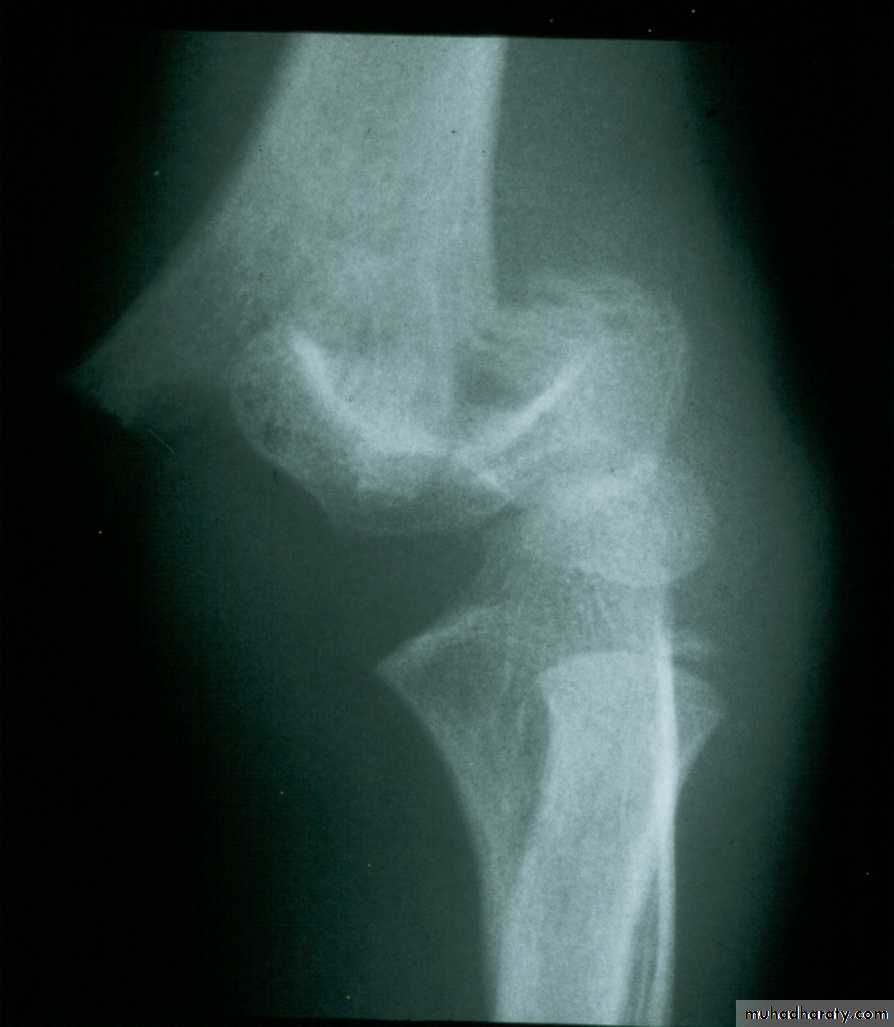

What are the criteria for

fractures?How are Type III extension supracondylar

fractures sub-classified?Yes

Posteromedial vs. Posterolateral

• Nerve, Vessel Injured

• Surgical Approach

• Rate of Complications

In what aspects is there a difference?

What type has a greater

potential for complications?

The rate of complications is greater with the posterolateral fractures.